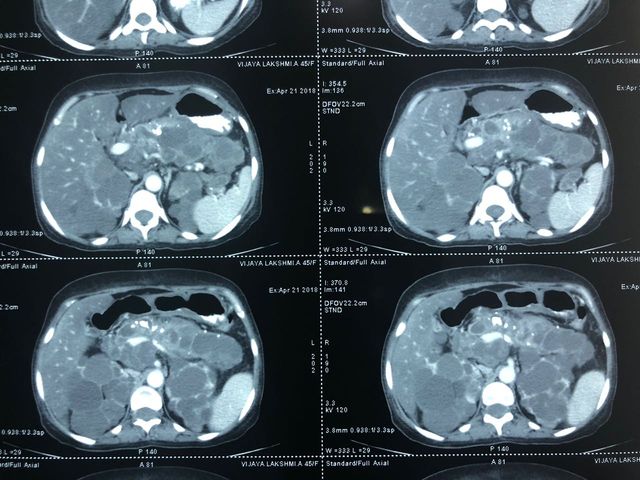

Cystic neoplasm of Pancreas

Middle aged female patient came with complaints of chronic upper abdominal pain since 6 months. The pain was mild to moderate, dull aching, non-radiating and not related to meals or defecation. It was not associated with vomiting, jaundice or abdominal lump. CT Abdomen suggested a cystic lesion in the distal body of pancreas of size 3x3 cm without communication with PD. Endoscopic Ultrasound guided Fine-needle aspiration (FNA) was performed and aspirated fluid suggested elevated CEA levels to 1168 with elevated amylase and lipase with mucin stain positive. Patient underwent laparoscopic spleen preserving distal pancreatectomy (Warshaw's technique). The resected specimen suggested mucinous cystadenoma of pancreas. The patient is asymptomatic now.